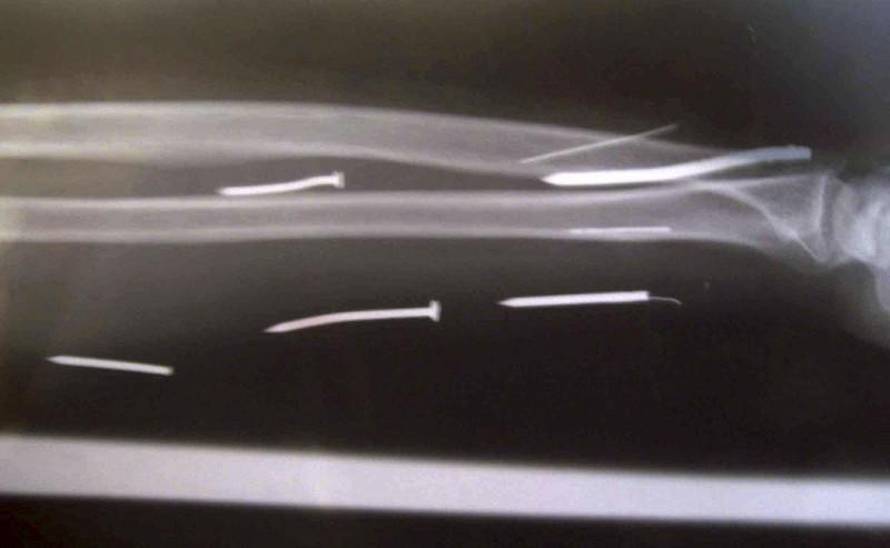

Sluškinja Ariyawathie (50) iz Šri Lanke pobjegla je od okrutnog poslodavca. Liječnici su joj izvadili 23 čavla iz tijela. Gazda ih je vjerojatno prije zagrijao